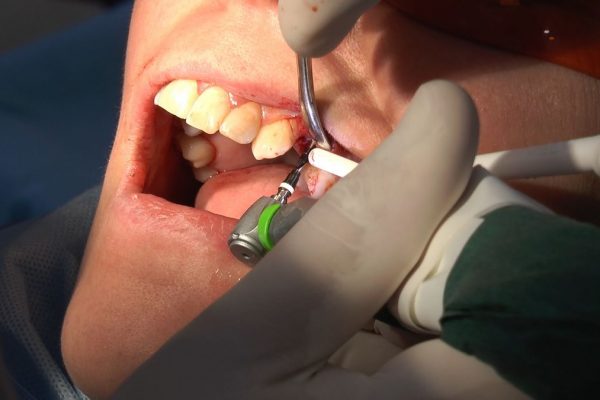

W ostatni weekend czerwca 2018 roku kursanci II Sezonu Preludium Implantologii odbyli piątą, finałową sesję, która w całości podporządkowana była praktyce. W ciągu dwóch dni zabiegowych Lekarze uczestniczący w szkoleniu przeprowadzili szereg zabiegów pod kierunkiem dr n.med. Violetty Szycik. Wszczepili 17 implantów oraz przeprowadzili ekstrakcje i zabiegi regeneracyjne kości. Zabiegi były wykonywane także w sedacji dożylnej z udziałem specjalisty anestezjologii i intensywnej terapii dr Jolanty Grzybowskiej. Preludium implantologii to nowy program edukacyjny dla adeptów implantologii stomatologicznej, którego celem jest wprowadzenie do implantologii poprzez pozyskanie wiedzy w szerokim zakresie i uwzględnieniem szczegółów mających decydujące znaczenie dla powodzenia leczenia implantologicznego. Ale tak jak wszystkie szkolenia w Instytucie Vivadental, w tym wiodące Practiculum Implantologii, zorientowane jest na praktyce i samodzielnym wykonywaniu zabiegów pod kierunkiem Mentora. To najlepsza edukacja w medycynie zabiegowej, a zarazem najlepszy start do implantologii.